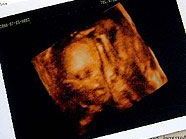

“Wenn die noch nicht mal so was unkompliziertes wie Dokumentation auf die Reihe kriegen, lässt das nichts Gutes für die Zukunft verheißen”, sagte der Mann, der anonym bleiben wollte. “Wir waren am Boden zerstört. Wir hatten unsere Embryonen schon durch das Mikroskop gesehen.”